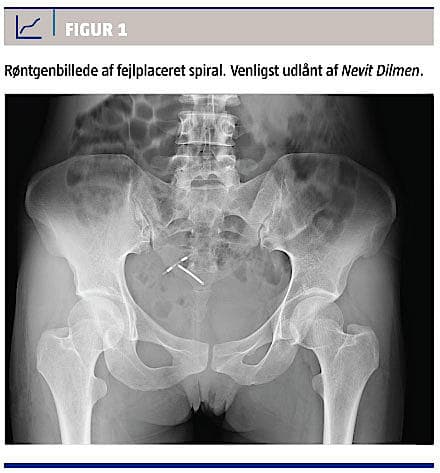

Kan en spiral ikke ses ved vaginal eller abdominal ultralydskanning, bør man foretage røntgenoversigt over abdomen (Figur 1). Alle spiraler indeholder røntgenfast materiale [5]. Det vil ofte være vanskeligt med sikkerhed at se spiralekko ultrasonisk uden for uterus, hvorfor ultralydskanning af abdomen ikke er en velegnet undersøgelse til at finde en forsvundet spiral.